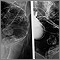

Enema opaco

Es una radiografía especial del intestino grueso, que abarca el colon y el recto.

El bario debe llenar el colon de una manera uniforme, mostrando una forma y posición intestinal normales, sin obstrucciones.